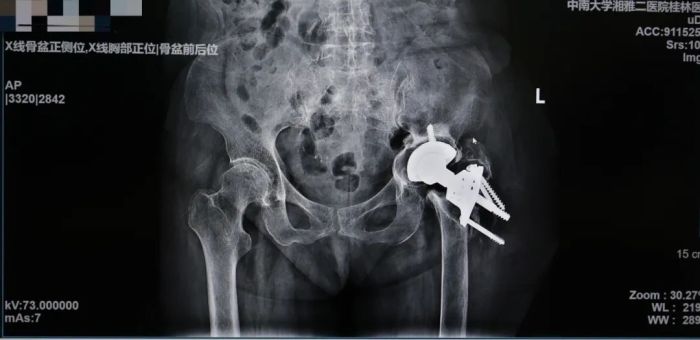

患者韦奶奶术后影像检查结果